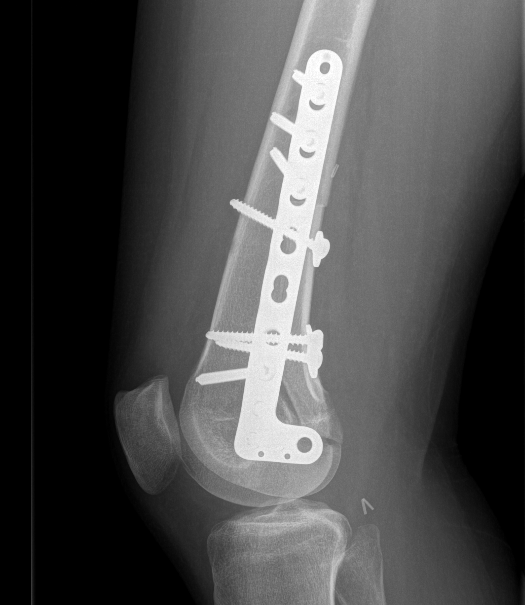

Parosteal Osteosarcoma proximal tibia

A. Hemicortical resection and posterior hemicortical allograft reconstruction